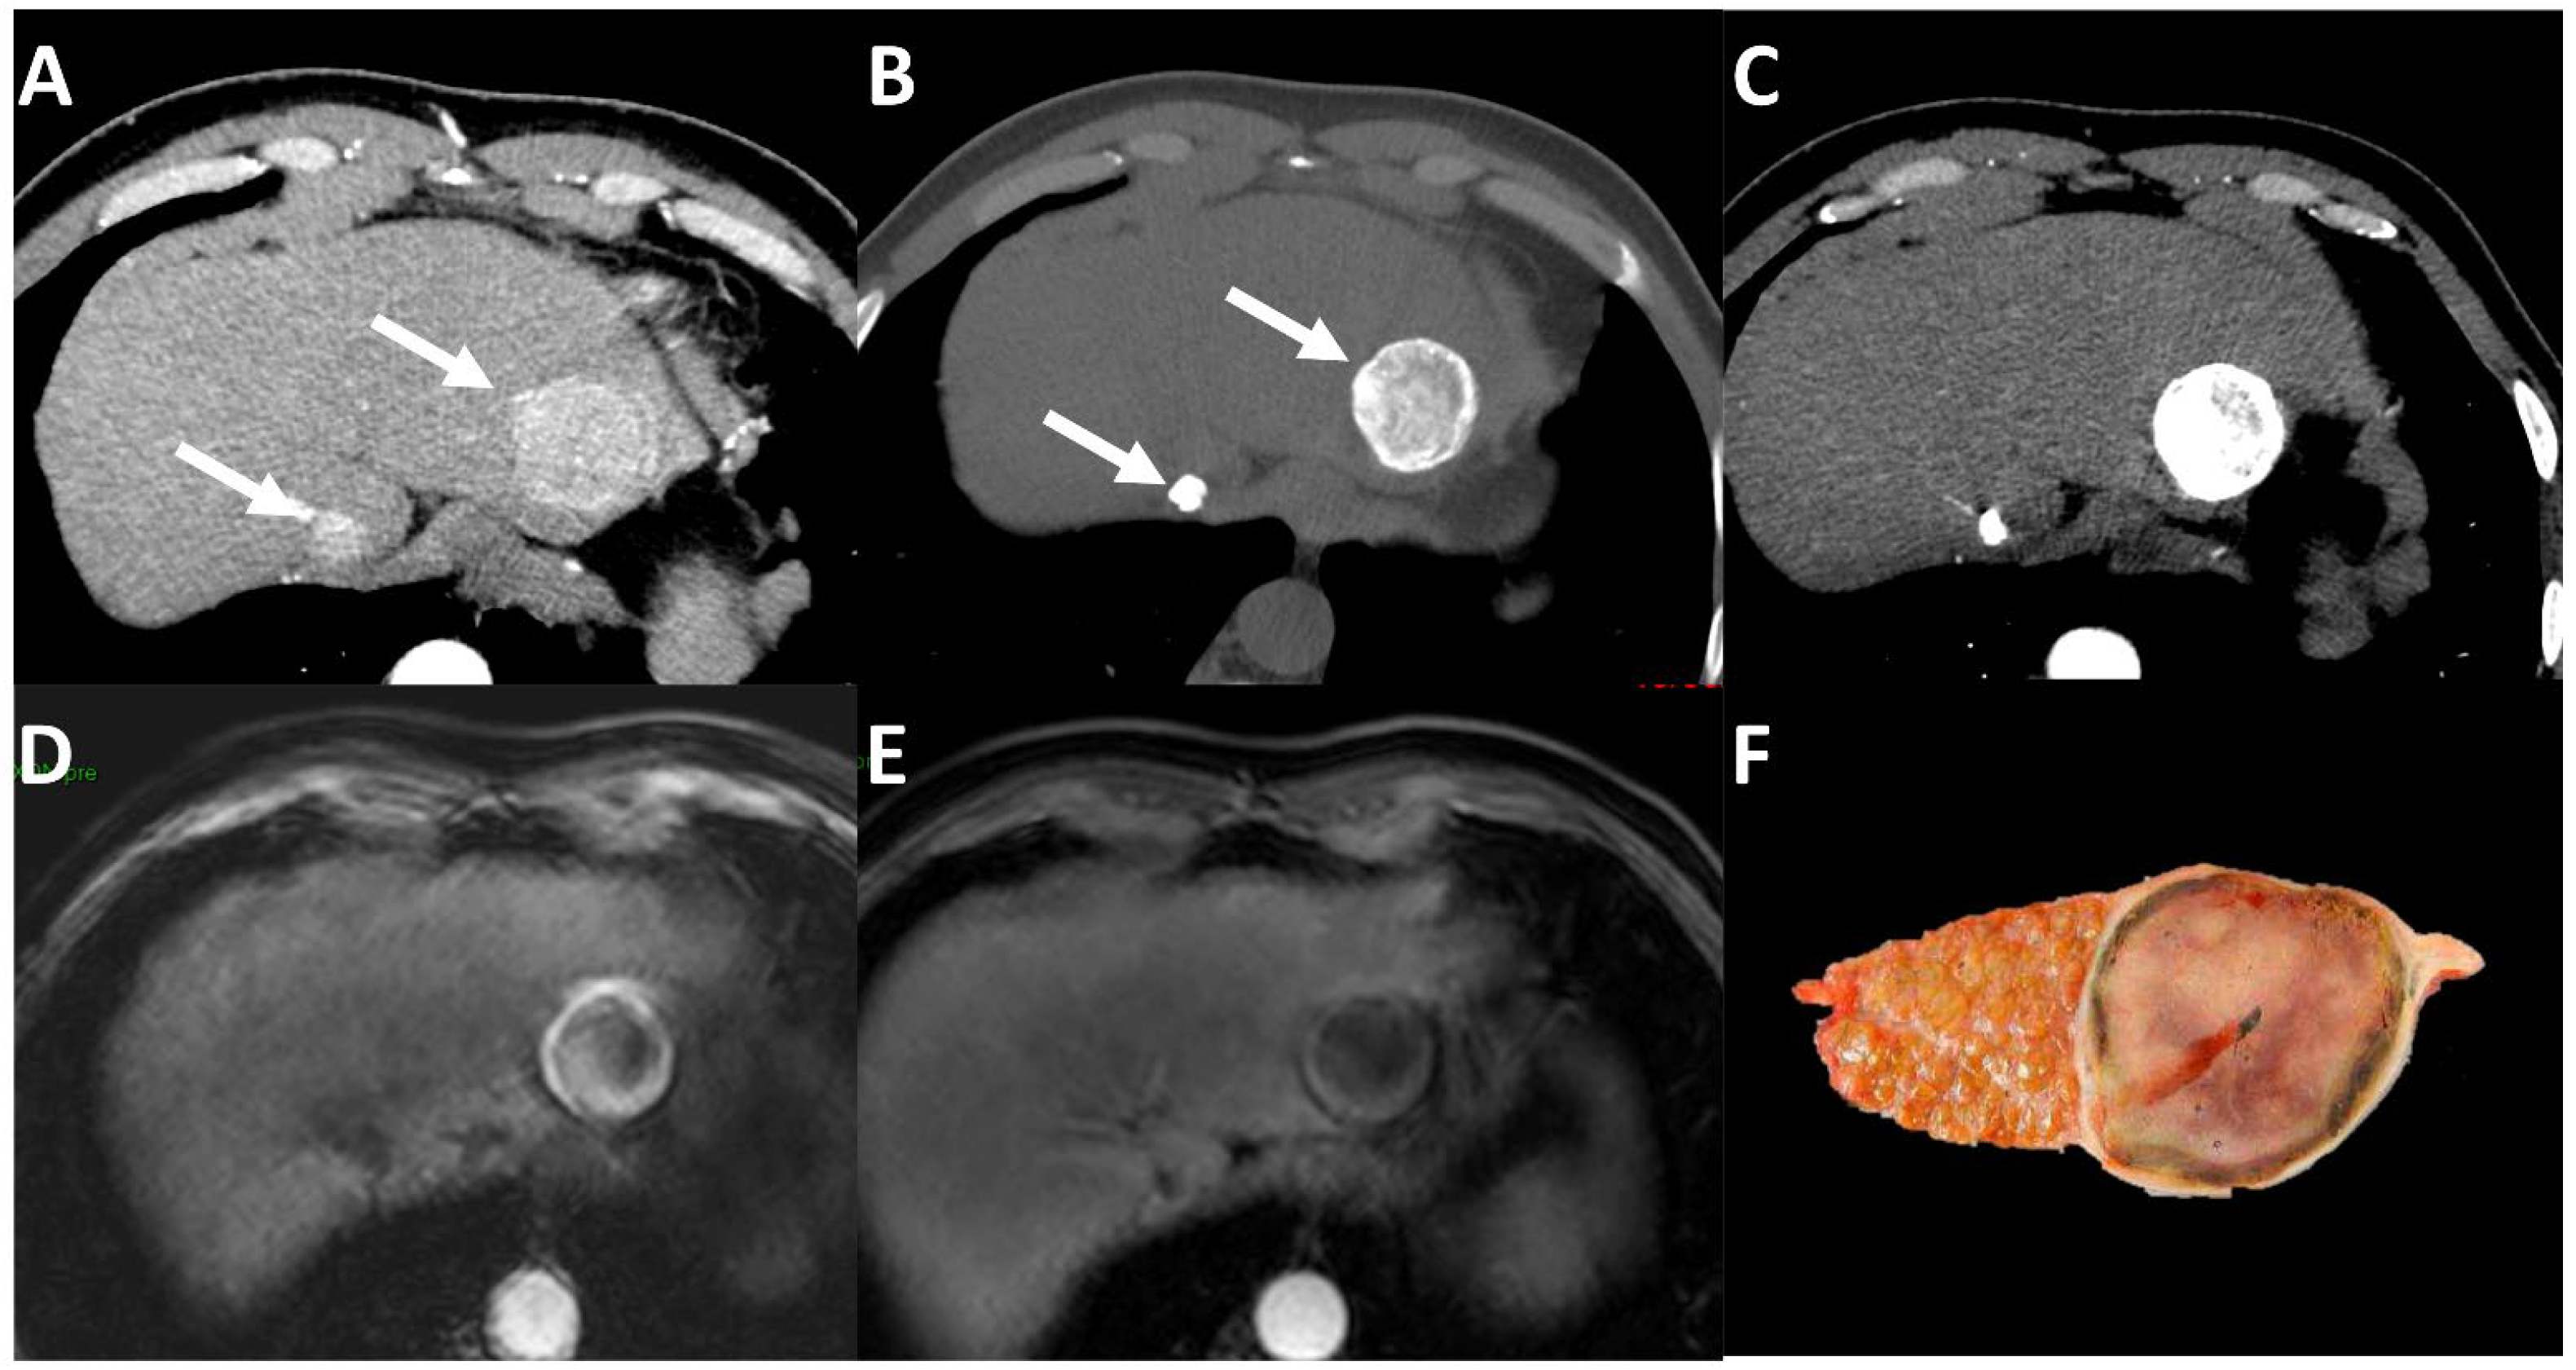

- Cannella, R.; Burgio, M.D.; Beaufrère, A.; Trapani, L.; Paradis, V.; Hobeika, C.; Cauchy, F.; Bouattour, M.; Vilgrain, V.; Sartoris, R.; et al. Imaging features of histological subtypes of hepatocellular carcinoma: Implication for LI-RADS. JHEP Rep. Innov. Hepatol. 2021, 3, 100380. [Google Scholar] [CrossRef]

- Feng, Z.; Li, H.; Zhao, H.; Jiang, Y.; Liu, Q.; Chen, Q.; Wang, W.; Rong, P. Preoperative CT for Characterization of Aggressive Macrotrabecular-Massive Subtype and Vessels That Encapsulate Tumor Clusters Pattern in Hepatocellular Carcinoma. Radiology 2021, 300, 219–229. [Google Scholar] [CrossRef] [PubMed]